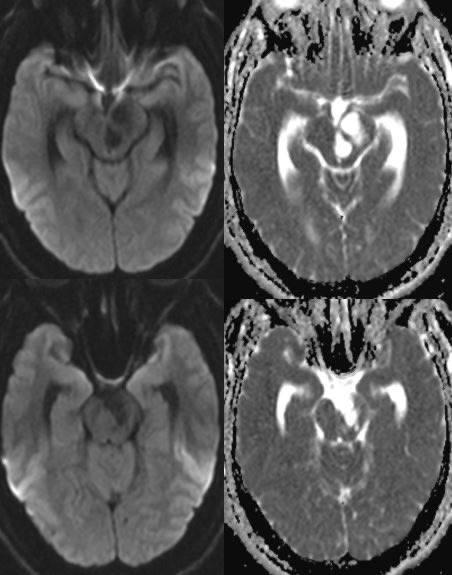

What is the most likely diagnosis in this 30 y/o M presenting with headaches? 🧠

🔷More images in 🧵